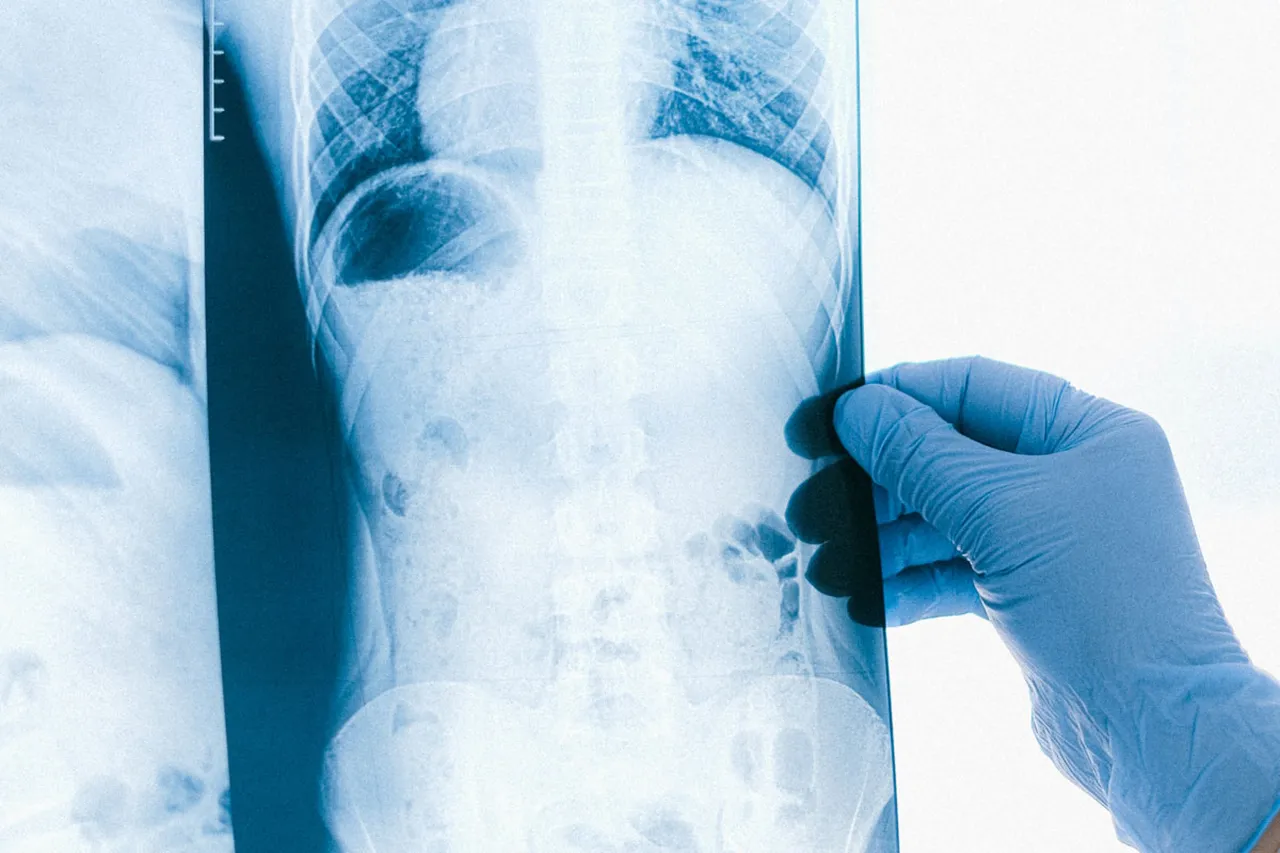

1 milyonda yılda 7 kişide görülen omurilik zarı tümörü tespit edilen Türkmenistanlı Hamid Mamedov, 6 saatlik operasyonla sağlığına kavuştu.

İstanbul'da yaşayan bir çocuk babası 38 yaşındaki Mamedov'a, 7 ay önce göğüs ağrısı şikayetiyle hastaneye başvurdu. Mamedov’a omurilik zarı tümörü tanısı konuldu. 1 milyonda yılda 7 kişide görülen omurilik zarı tümörü tanısı konulan Mamedov, ameliyat için İstanbul'dan Kars'a geldi. Mamedov, 6 saatlik ameliyatla omurilik zarındaki tümörden kurtuldu.

Ameliyatı yapan Beyin ve Sinir Cerrahisi Uzmanı Operatör Dr. Meftun Zerbizade "Bu tümör, dünya literatüründe 1 milyon kişide yılda 7 hastada görülebiliyor, yani oldukça nadir görülen tümör. Hastanemizdeki ameliyathane şartlarını, cerrahinin isteğine uygun, çok güvenli ve rahat şekilde düzenleyerek ameliyatı yaptık" dedi.